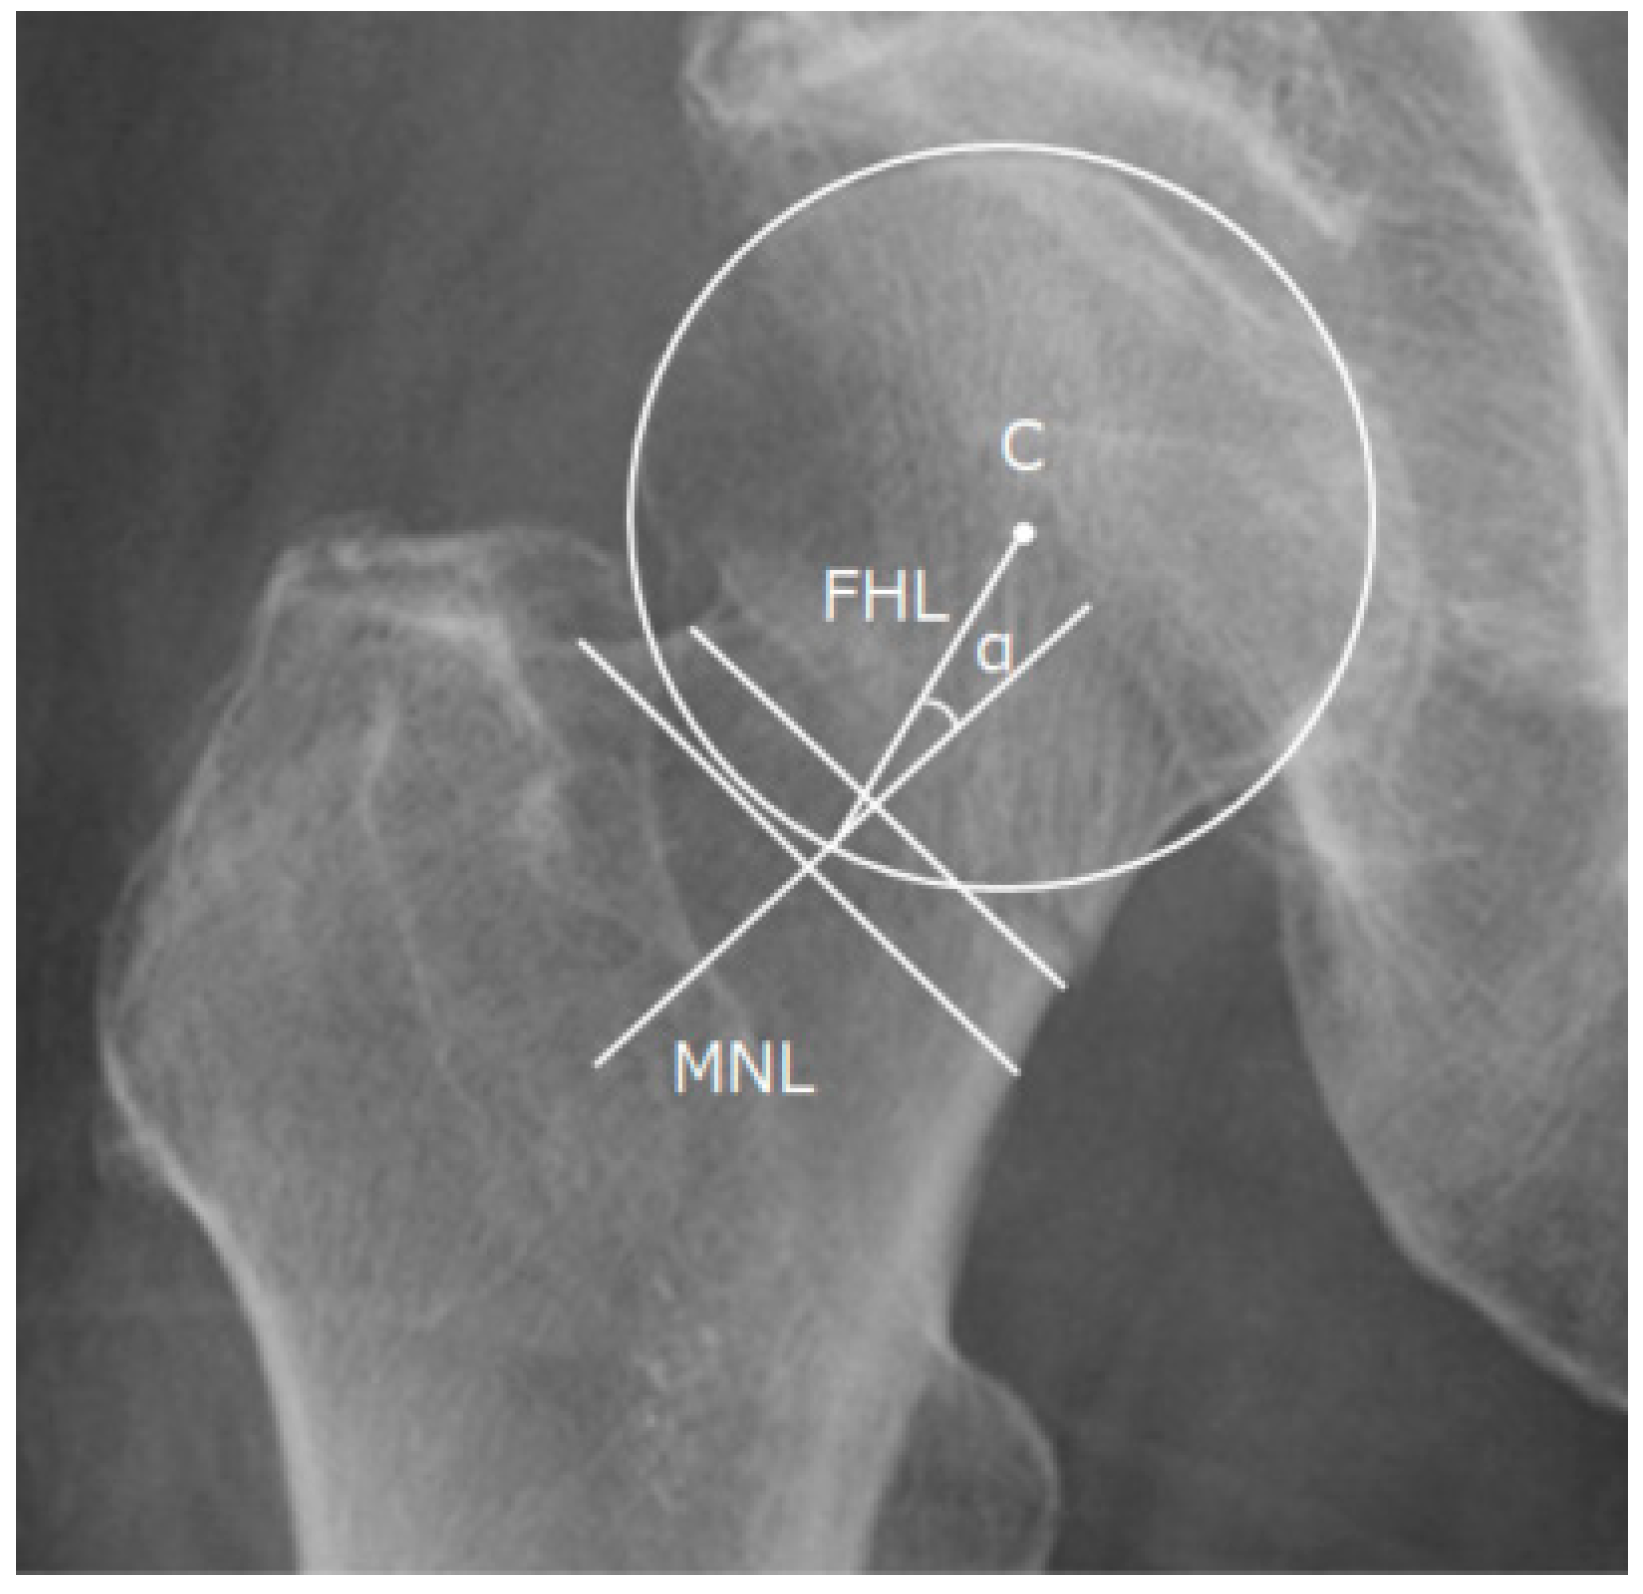

2.6. Valgus Tilt Measurement